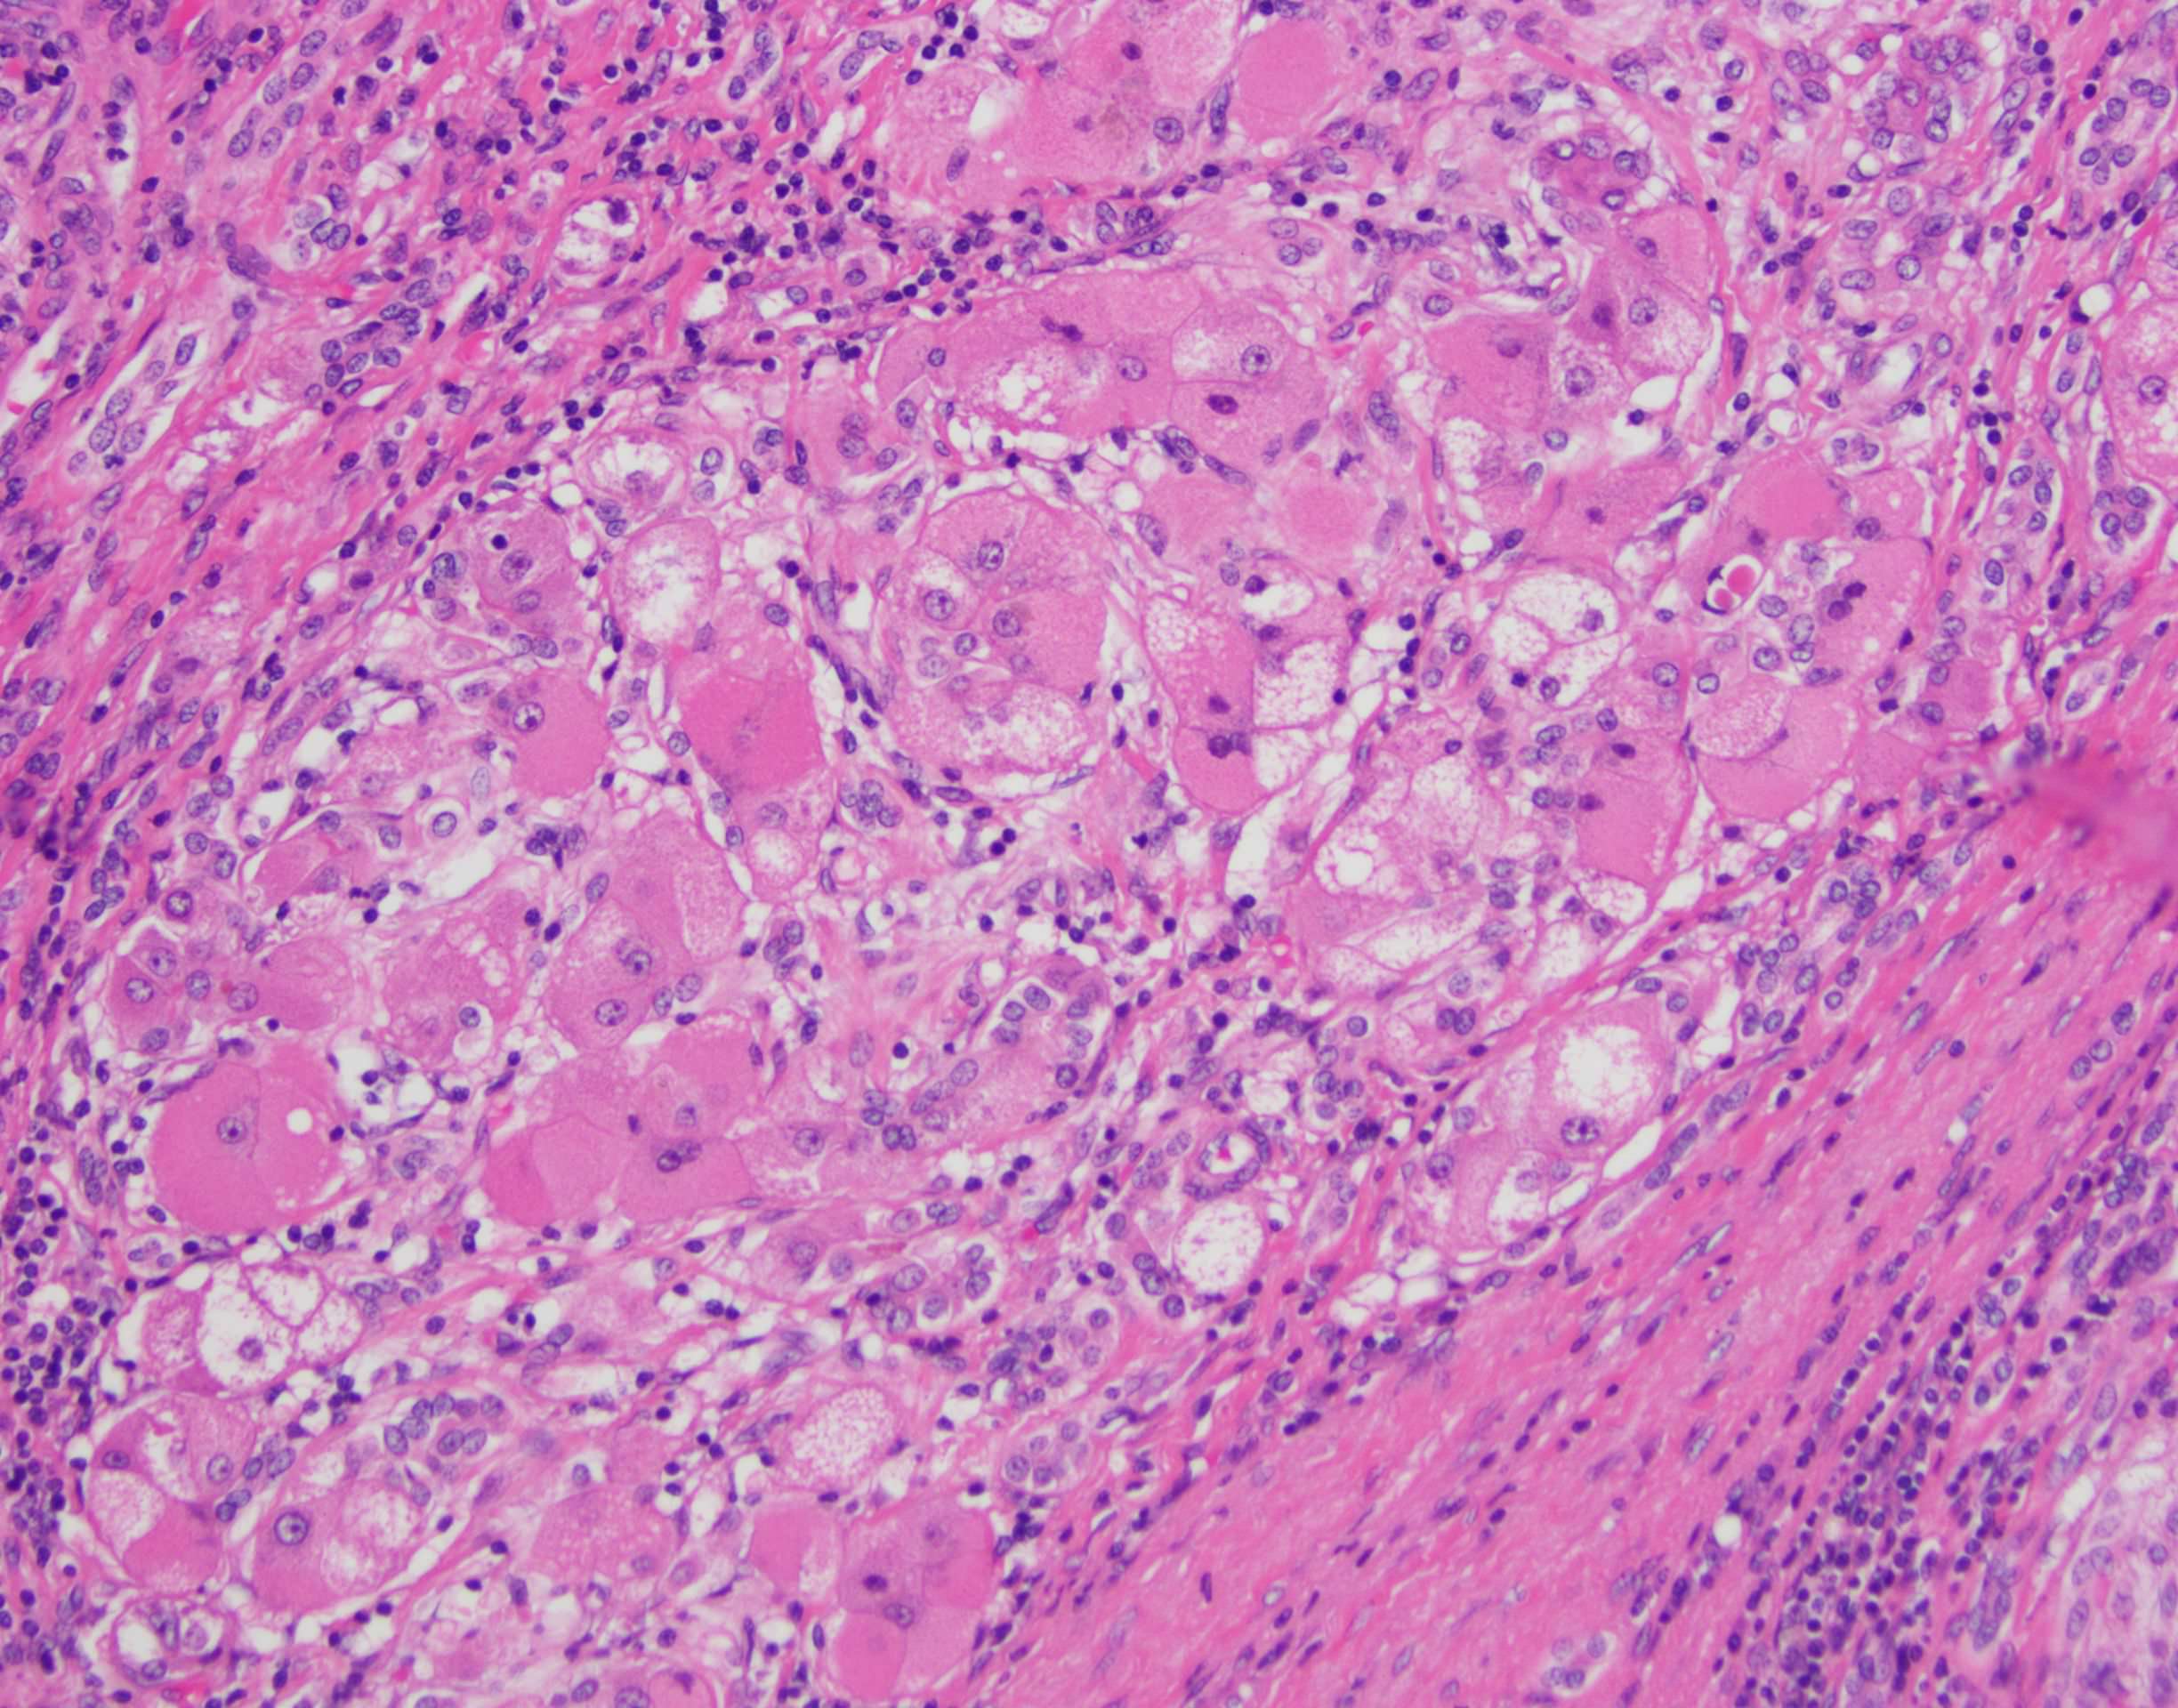

- Large cell change is defined as an increase in both nuclear and cytoplasmic size, preserving nuclear to cytoplasmic ratio; nuclei are hyperchromatic, pleomorphic and frequently multinucleated

- Small cell change is defined as hepatocytes showing decreased cell volume, increased nuclear to cytoplasmic ratio, mild nuclear pleomorphism, hyperchromasia and cytoplasmic basophilia, giving the impression of nuclear crowding; this pattern is typical of high grade dysplastic nodules